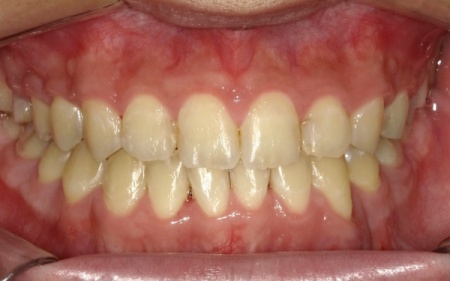

10代男性 顎変形症が原因で下顎がずれて非対称になっていた噛み合わせをサージェリーファースト法を併用した矯正治療で改善した症例

「顔と顎がゆがんでいて、見た目が悪くしゃべりにくいのが気になる。また、前歯が噛み合っていないため、食べ物を噛み切ることができない」とご相談いただきました。

拝見したところ、骨格の問題により下前歯が上前歯より前に出ている前歯部反対咬合と、前歯が開いて噛み合わないオープンバイトが認められました。

さらに、下顎の骨が右方向にずれて上下の歯が噛み合う面が斜めになっていることで、顔面の非対称も見られます。

これらは顎変形症と呼ばれる状態で、現在は食べ物をしっかりと噛む機能が大きく制限されているうえ、発音や見た目に悪影響が出ていました。